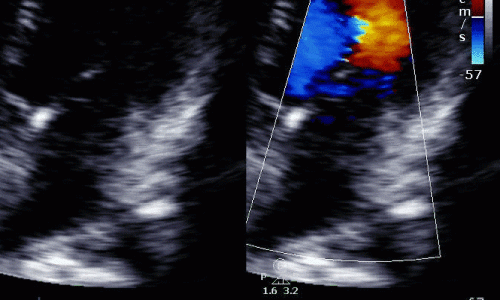

Mechanical Complications of STEMI

Unfortunately not every patient that suffers a STEMI makes a complete recovery, even if treated with primary PCI. Patients that present late into their infarct have a higher risk of developing a complication.

Here are two cases that illustrate the spectrum of mechanical complications that can occur in the aftermath of an infarct.